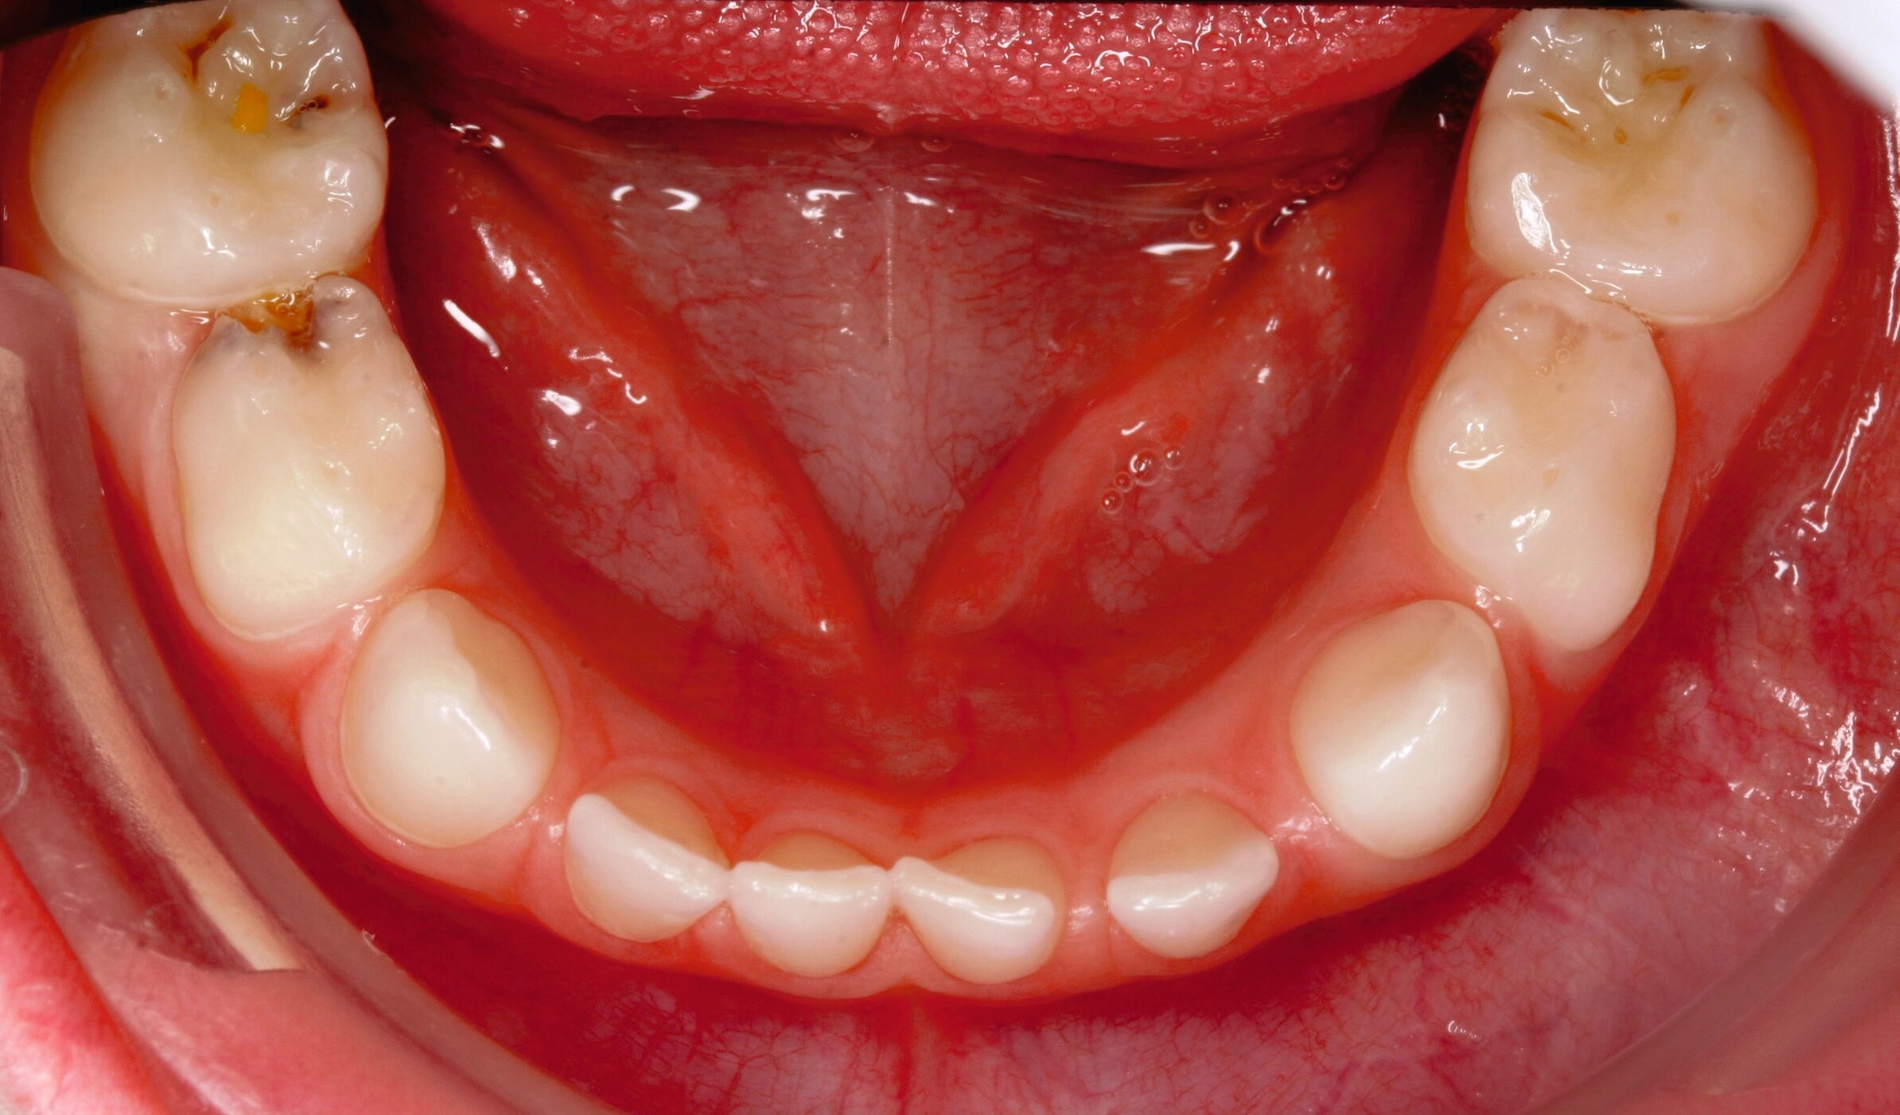

Zentrales Problem bei der Milchgebisskaries ist aber nicht dieser Mineralverlust oder der Defekt, sondern die „übergroße“ Pulpa, die häufig mit betroffen ist (Abbildung 2), bei oftmals zugleich geringer Kooperationswilligkeit oder -fähigkeit der Kinder für invasive Eingriffe. Damit ist bei kariösen Defekten an Milchzähnen die korrekte Diagnose zum Zustand der Pulpa beziehungsweise die Abschätzung der Pulpabeteiligung der kariösen Läsion die primäre und wichtigste Aufgabe. Dies ist allerdings bei Kleinkindern über die Schmerzanamnese und die Röntgenbilder häufig nicht valide möglich. Es gibt zwei Möglichkeiten, dieses Dilemma zu lösen:

Die klassische invasive Lösung mit („diagnostischer“) Pulpotomie, visueller Beurteilung des Pulpazustands und nachfolgender Versorgung mit einer Stahlkrone: Die Invasivität dieser Maßnahmen bedingt allerdings bei vielen kleinen Kindern eine komplexe Zahnbehandlung in Narkose.

Die Kariesinaktivierung und Verlaufskontrolle über die Zeit: Wenn die Läsion sich erkennbar remineralisiert und der Zahn schmerzfrei sowie ohne Fistel/Abszess bleibt, liegt offensichtlich nur eine reversible Pulpitis vor.

Alle irreversiblen Pulpitiden oder gar Pulpanekrosen bedingen eine endodontische oder eine Extraktionstherapie des Milchzahns. Bei beiden Ansätzen sind der kariöse Defekt, seine Ausdehnung oder die Kariesentfernung das eindeutig sekundäre Problem, die Kooperation des Kindes bei diesen Maßnahmen ist dafür umso entscheidender. Im Folgenden sollen diese einzelnen Therapiepfade detaillierter dargestellt werden.